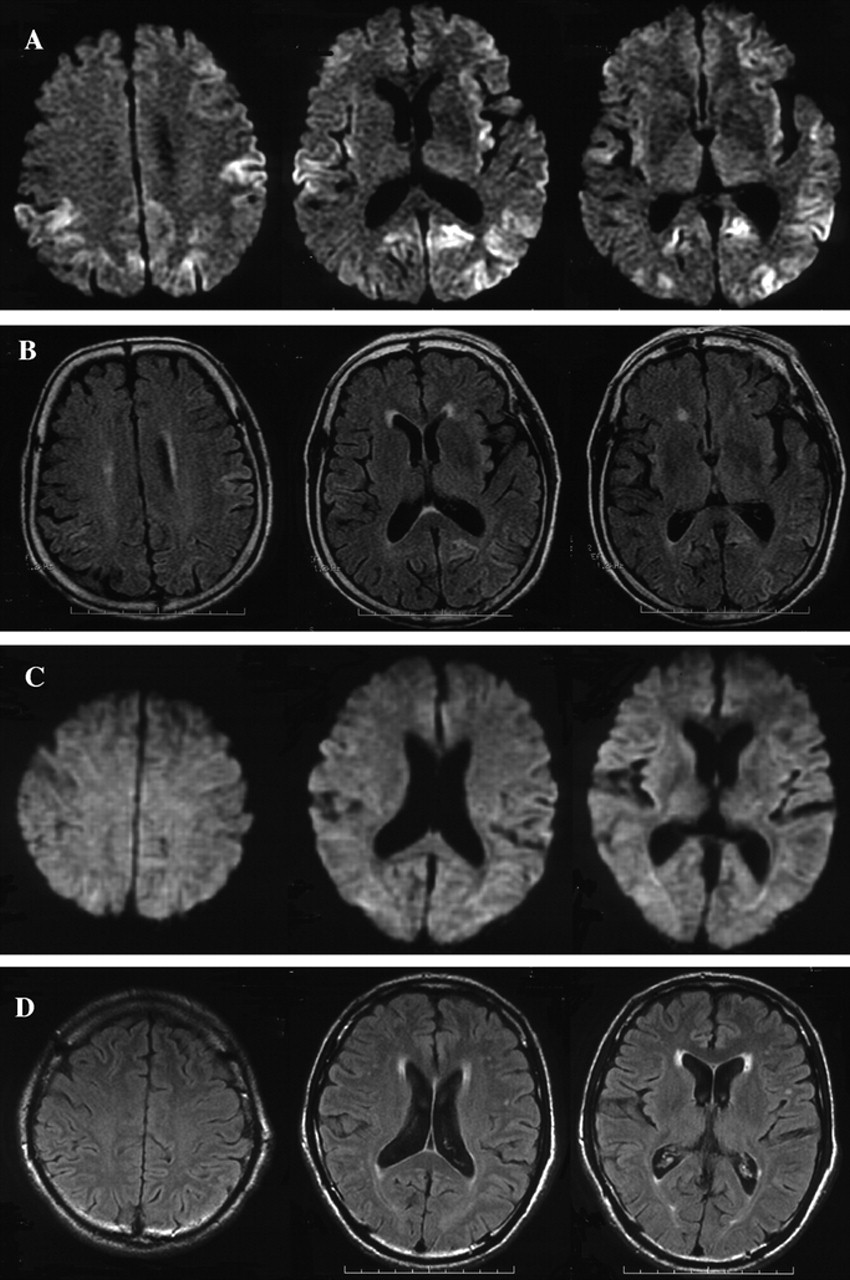

图2。SPECT脑血流量(CBF)使用99米Tc-ethyl cysteinate二聚体在16个月后病人2 (A),病人发病8在7个月后(B),和一个正常的控制问题是一个67岁的老人没有神经异常和认知能力衰退(C)。SPECT显示两国在患者的颞叶皮层的CBF减少2 (A)和双边丘脑以及颞叶皮层在病人8 (B)与正常相比控制(C)。

16个月后,MRI显示gyriform hyperintensity双边额叶,颞顶叶和枕叶皮层在diffusion-weighted成像(驾车)(图1一个)。那么激烈,皮质病变显示在小fluid-attenuated反转恢复成像(见图1 b)。脑电图,漫射放缓没有PSWCs被发现。CBF-SPECT使用99米Tc-ECD显示减少的CBF双边顶叶和颞皮层(图2一个)。脑脊液检查发现14-3-3蛋白水平增加(28 ng / mL(正常< 20 ng / mL))。尽管sCJD的临床标准20.并不满足,因为缺乏神经和脑电图异常,怀疑库贾氏症MRI和CSF的基础上发现。

神经系统检查7个月后发现痴呆,小脑性共济失调,肌肉阵挛性抽搐,夸张的深部腱反射所有的四肢。脑部核磁共振成像,包括醉酒驾车,脑电图正常(见图1中,C和D)。CBF-SPECT使用99米Tc-ECD透露的CBF减少双边丘脑和皮质颞顶叶(见图2 b)。CSF研究披露轻微增加蛋白质的浓度(44 mg / dL)和模棱两可的14-3-3蛋白水平。阿尔茨海默病(AD)的诊断是怀疑。

平方毫米的情况下丘脑的形式,发病年龄范围从30到71年,临床过程的持续时间从13到73个月(见表1)。临床表现包括精神病症状,痴呆,小脑性共济失调、失眠、和自主失败(见表1)。至于FFI的突出特点和SFI,失眠在只有一个病人(病人4),和自主症状被发现在三个病人(病人4、5、7)。脑电图显示没有PSWCs除了一位病人(病人6)显示PSWCs很晚阶段(见表2)。这些特性与先前报道的患者数目丘脑3或者你以后。8、10脑部核磁共振成像,包括醉酒驾车,几乎是正常的平方毫米丘脑的患者除了脑萎缩或白质后期的变化(见表2)。这些功能与以前的报道相一致SFI患者。8、10在我们的研究中,两个病人检测CSF 14-3-3蛋白,一个是积极的,另一个是模棱两可(见表2)。在文献中,据我们所知,有报道称,4平方毫米丘脑sCJD患者检查脑脊液14-3-3蛋白:考试是积极的6和负三。7、8考虑这些报道与我们的结果,我们不能得出结论,CSF 14-3-3蛋白诊断平方毫米丘脑sCJD足够敏感。最初的临床诊断,进行性核上的麻痹(PSP),脊髓小脑的变性(SCD),或广告一直怀疑(见表1),表示相当困难的临床诊断平方毫米丘脑的形式。然而,我们回顾CBF-SPECT研究显示特征的结果减少CBF的双边丘脑和大脑皮层的相对早期阶段(见表2)。在以前的报告CBF-SPECT研究库贾氏症病人,减少CBF的目视检查发现大脑皮层不同区域的但不是在丘脑。26日,27日没有关于CBF-SPECT平方毫米丘脑sCJD报告。在摄影的研究中,丘脑和大脑皮层的代谢减退患者SFI报道10或者在某些FFI患者。28、29CBF和丘脑葡萄糖代谢相对保存在广告。30.在PSP,显著减少葡萄糖代谢不是丘脑中发现,而是在额叶皮层通过地区检测到/枕的代谢率。31日多系统萎缩,零星的SCD的表型,减少丘脑CBF的报道;然而,显著减少CBF还检测到的背壳。32我们的患者数目丘脑sCJD没有CBF的壳(见减少图2 b)。我们的研究结果清楚地表明,减少双边丘脑CBF以及代谢减退,与他们的保护壳,将是一个特别有用的诊断为平方毫米丘脑sCJD标记。

Hyperintensity双边丘脑(枕符号)建立了核磁共振是一个有用的诊断标记vCJD症。33、34但是,没有在枕MRI异常信号中可以检测到MM2-type sCJD,如图所示在当前研究和在以前的报告。8、10CBF-SPECT研究在两个vCJD症患者表现出广泛的CBF减少大脑皮层花托的但没有明显的参与。26这些CBF-SPECT特性不同于那些在专业丘脑sCJD。我们的研究结果表明神经影像学研究的有效性之间的歧视和vCJD MM2-type sCJD。